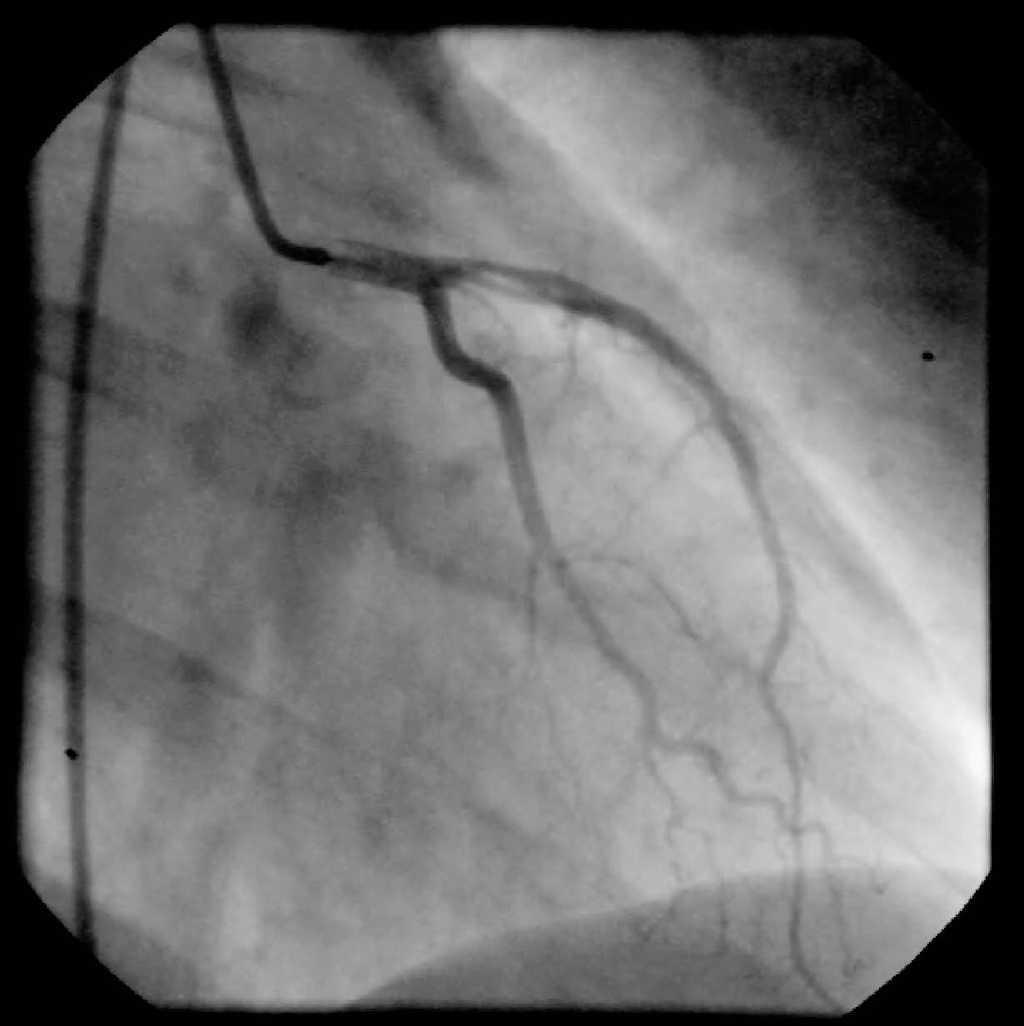

Acudió al Servicio de Urgencias por episodio de dolor torácico típico, encontrándose la paciente normotensa y evidenciándose en el electrocardiograma (ECG) taquicardia sinusal a 110 lpm y una corriente de lesión subepicárdica de V2 a V5 (fig. 1). En la exploración física no se objetivaron alteraciones, destacando en la analítica inicial leucocitosis con neutrofilia y troponina elevada.

Figura 1. Electrocardiograma de la paciente en el momento del ingreso.